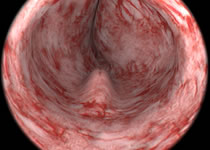

Resección transuretral de la próstata

La resección transuretral de la próstata (TURP, por sus siglas en inglés) es una cirugía para extirpar parte de la próstata.

La TURP se realiza cuando un hombre tiene un agrandamiento no canceroso de la próstata. Se denomina hiperplasia prostática benigna (HPB) . En la HPB, la próstata crece y se presiona contra la uretra y la vejiga. La presión puede causar problemas con el flujo normal de la orina.

También se puede realizar una TURP cuando un hombre tiene cáncer de próstata. El médico puede decidir realizarla si considera que una cirugía de extirpación de próstata completa es demasiado riesgosa. En este caso, la TURP se lleva a cabo para extraer una parte de la próstata a fin de aliviar la obstrucción de orina y disminuir los síntomas. No se realiza para tratar el cáncer en sí.